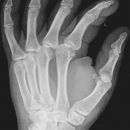

Handgelenk a.p.

Beurteilungskriterien

- Neigung der distalen Radiusgelenkfläche in der Frontalebene: 15 – 35°

- Längenverhältnis Radius – Ulna: Proc.styloideus radii überragt Gelenkfläche der Ulna um 9 –12mm (<9mm Ulna-Plusvariante, >12mm Ulnaminusvariante)

- Kontinuität der drei Karpalbögen:

Proximaler Bogen: proximale Gelenkflächenkonturen von Scaphoid, Lunatum und Triquetum

Mittlerer Bogen: distale Gelenkflächenkonturen von Sacphoid, Lunatum und Triquetum

Distaler Bogen: proximale Gelenkflächenkonturen von Capitatum und Hamatum

Fehlende Abgrenzbarkeit, Versatz oder Unterbrechung sind als pathologisch zu bewerten und deuten auf eine Luxation hin.

Trapezförmige Darstellung des Lunatum in Neutralstellung? Augenzeichen des Hamulus? Superposition von Pisiforme und Triquetum? Metacarpale III in Projektion innerhalb der Radiusgelenkfläche? Lunatum zu >50% über Radiusgelenkfläche? Cave: bei Radial- oder Ulnarduktion wandert das Lunatum in umgekehrter Richtung.

- M-förmiger Verlauf der Gelenkspalten der Carpometacarpalgelenke? Luxationsstellung in den Carpometacarpalgelenken (meist dorsale Luxation)?

- Gelenkspaltweiten des Radiocarpalgelenk 2 – 2,5mm, der Carpometacarpalgelenke 1 –2mm, distales Radioulnargelenk 2mm, Gelenksspaltweiten der Intercarpalgelenke 1,5 – 2mm

Cave: SL-Dissoziation (Ruptur des SL- Bandes, häufigste Gefügestörung): Terry-Thomas-Sign = SL-Spalt > 3mm, Siegelringzeichen = Ringförmige Transparenzminderung im mittleren Scaphoiddrittel durch orthograde Projektion der Taille infolge Rotation.

- Obliteration des Scaphoidfettstreifens?

- Täuschungsmöglichkeiten durch Vielzahl akzessorischer Ossikel (abgerundete, zirkulkär-geschlossene Kortikalis), geteilte Handwurzelknochen (Scaphoid, Lunatum, Pisiforme) und Gefäßkanälchen

- Target areas leicht zu übersehender Frakturen: distales Radioulnargelenk, Processus styloideus radii et ulnae, Basen der Metacarpalia (v.a. MCP I), Hamulus.

- Grundsätzlich gilt: unklare Verhältnisse ->CT-Indikation